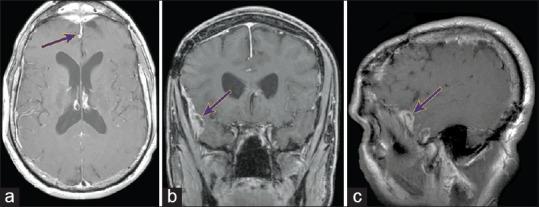

Esthesioneuroblastoma is a locally aggressive cancer of the nasal cavity. While systemic metastasis can occur in 10-30% of patients, there are only six reported cases of distal metastasis from leptomeningeal dissemination.

The authors report two cases of esthesioneuroblastoma treated previously with multimodal therapy in which distal metastatic recurrence was found and describe their treatment protocol, which has resulted in long-term success.

嗅神经母细胞瘤是鼻腔的一种局部侵袭性癌症。虽然10% - 30%的患者可能发生全身转移,但仅有6例经软脑膜播散导致远处转移的报道。

作者报告了2例先前接受多模式治疗的嗅神经母细胞瘤病例,其中发现了远处转移性复发,并描述了他们的治疗方案,该方案已取得长期成功。